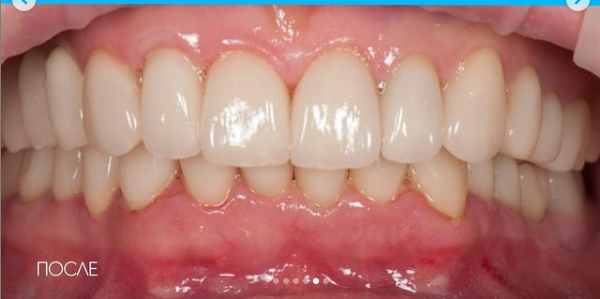

Установка коронки из диоксида циркония

Протезирование на свои зубы с помощью коронок из диоксида циркония и коронок ЕМАХ

Доктор: Новожилов Алексей Александрович